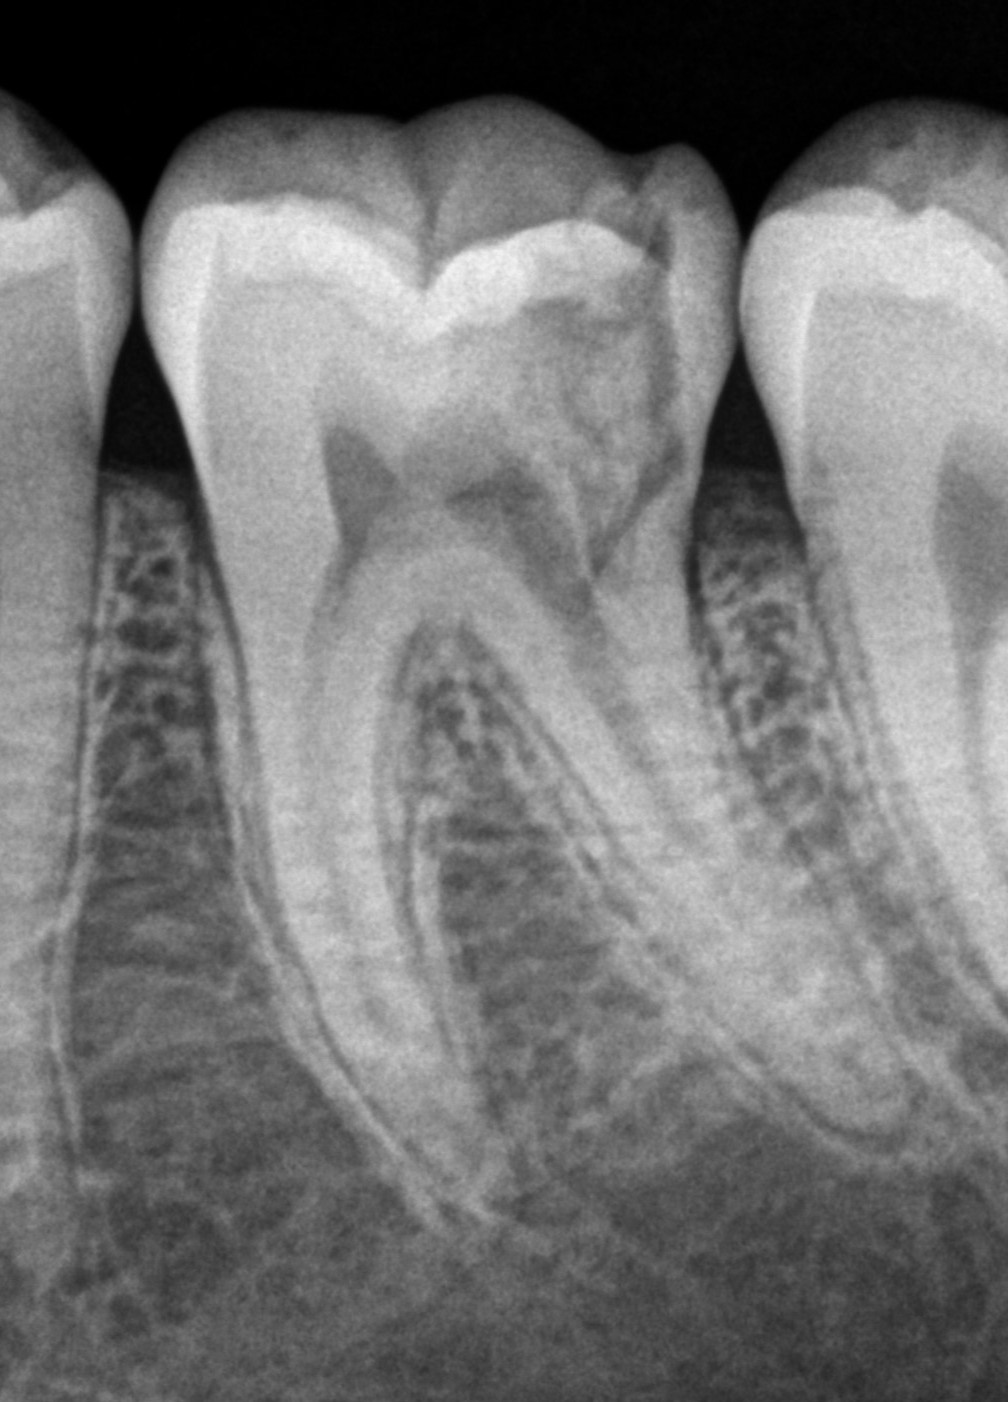

See My Work

Cases